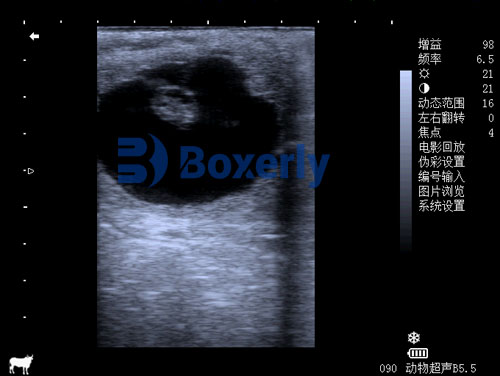

Ultrasonography employs high-frequency sound waves to create images of internal structures. In equine reproduction, transrectal ultrasonography is commonly used to visualize the uterus and ovaries. This method provides real-time images, enabling veterinarians to assess the presence of an embryo, monitor fetal development, and identify any abnormalities.

Approximately two weeks post-ovulation, the first ultrasound is performed to confirm pregnancy by identifying the embryonic vesicle. This examination is also crucial for detecting twin pregnancies, which pose significant risks. If twins are identified, one embryo is typically reduced to enhance the chances of a successful single pregnancy.

Around the fourth week, a follow-up ultrasound assesses the embryo's viability by detecting a heartbeat. This milestone indicates a progressing pregnancy and helps identify any early embryonic losses.